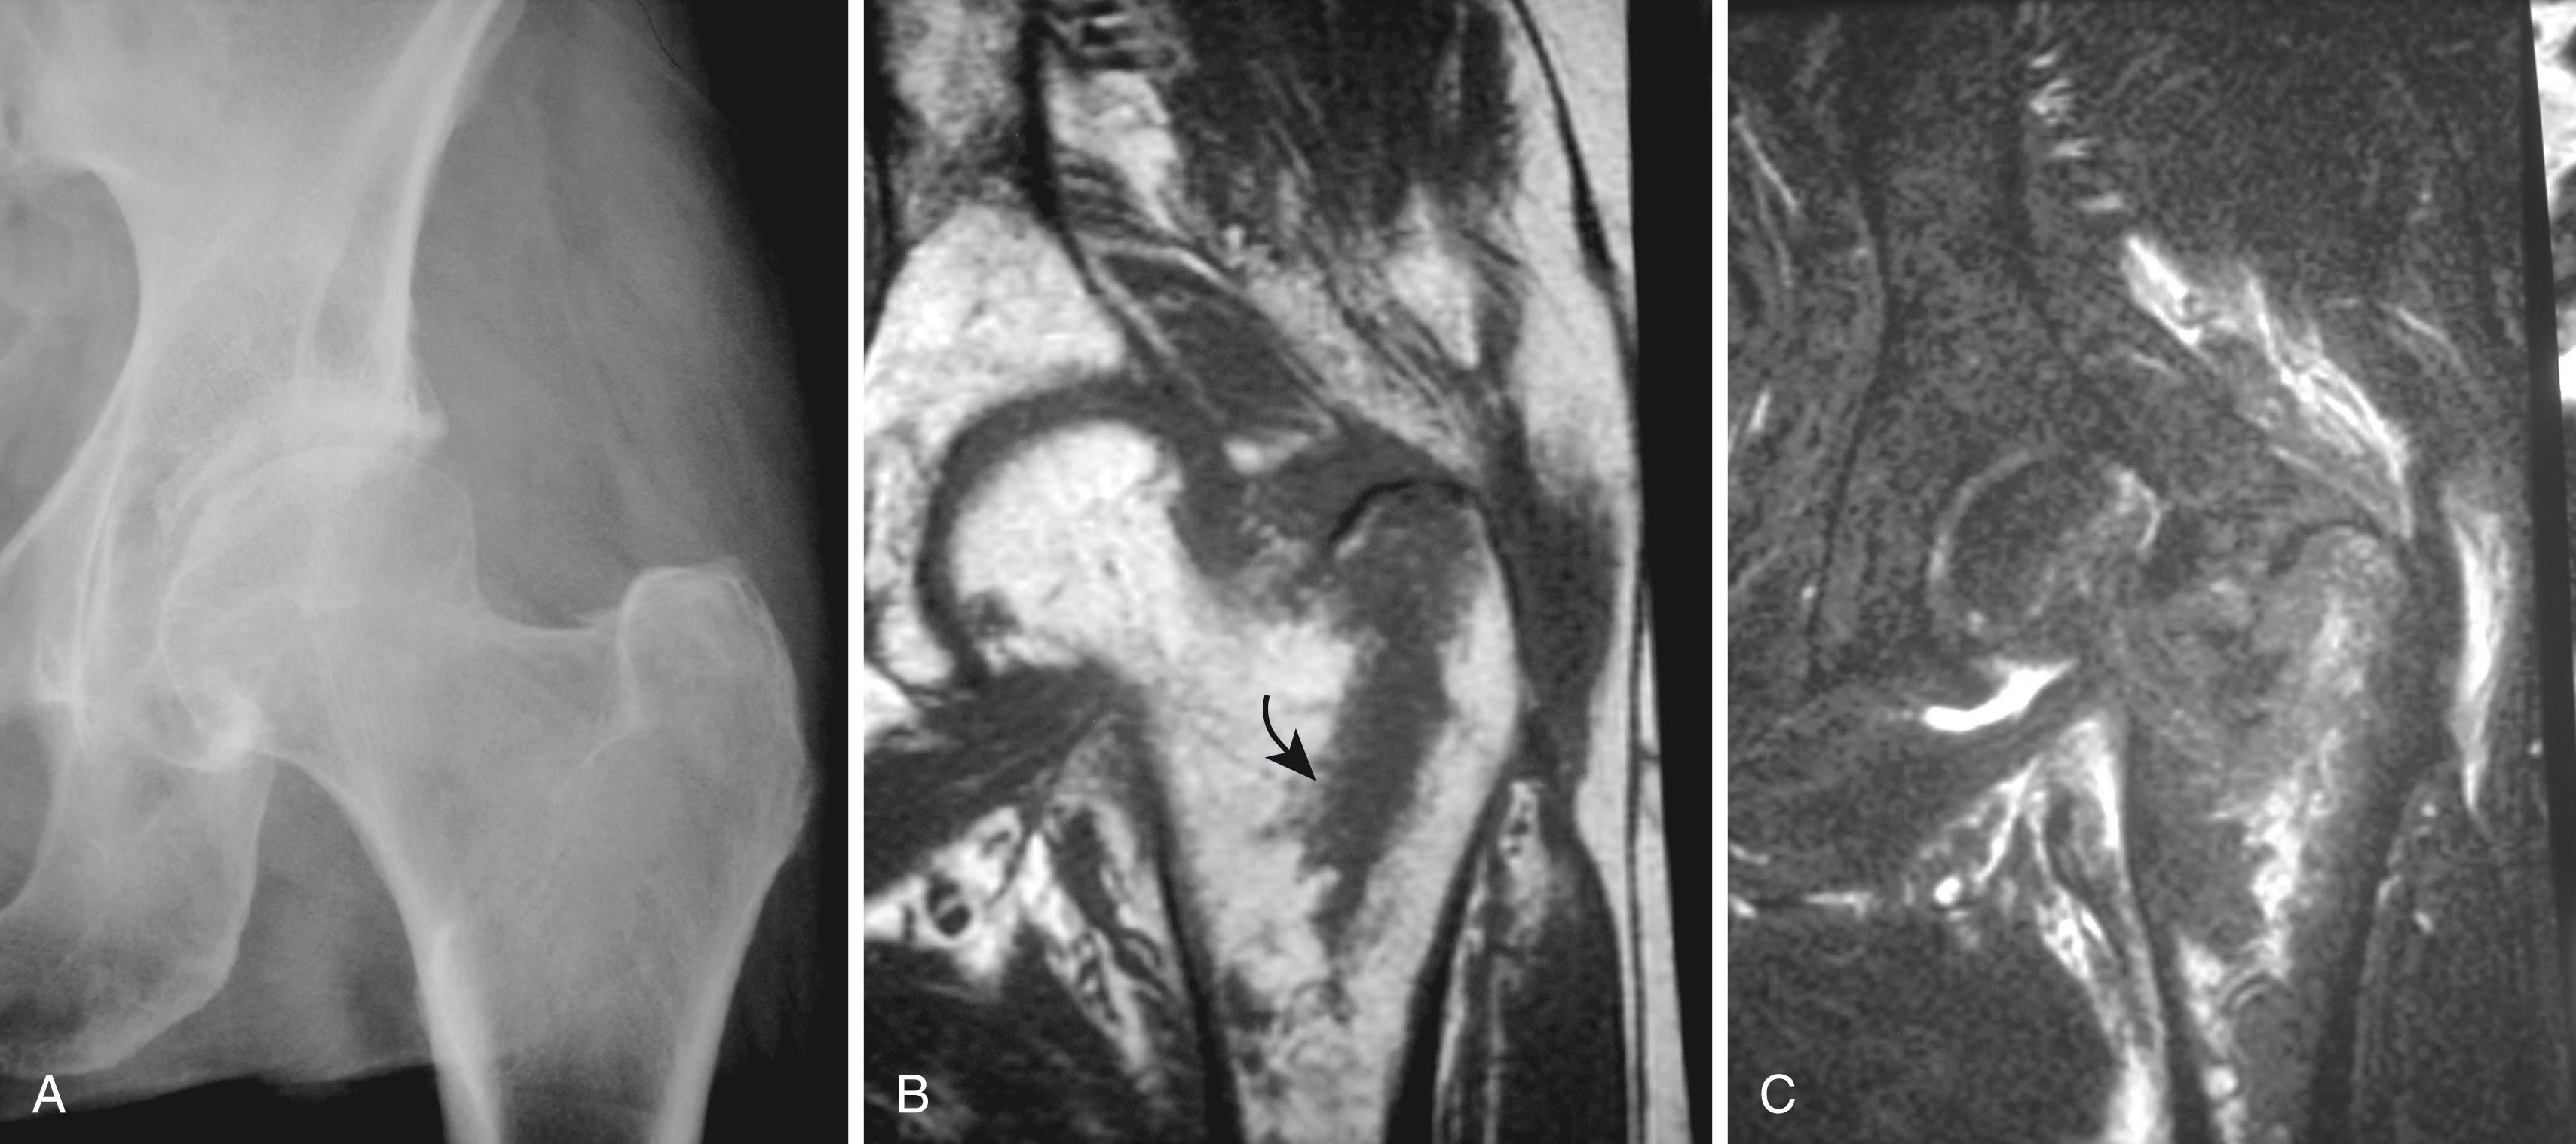

Frequently, MRI can be helpful in evaluation of the hip after trauma. Radiographs are often negative or equivocal for fracture of the proximal femur in elderly individuals. Although bone scintigraphy has been used to confirm or exclude fracture, this study can be falsely negative in elderly patients in the first 48 hours after injury. The MRI abnormalities are immediately apparent, with linear areas of low signal easily seen in the fatty marrow on T1-weighted images and surrounding edema seen with T2-weighted images ( Fig. 2.28 ). In addition, the anatomic information provided can assist in determining the type of fixation required. In fact, many radiographically occult fractures subsequently discovered by MRI are confined to the greater trochanter or incompletely traverse the femoral neck and, in certain patients, may be treated conservatively.

FIGURE 2.28, Radiographically occult proximal femoral fracture in elderly woman. A, Questionable cortical disruption is noted on radiograph of left hip obtained after fall. B, Coronal T1-weighted image confirms greater trochanter fracture manifested as vertically oriented band of reduced signal (curved arrow) within normal bright fat signal of femoral neck. C, Coronal inversion recovery sequence shows edema at fracture.

A great deal of effort has been directed at the imaging evaluation of femoroacetabular impingement and the acetabular labrum. Original reviews of the accuracy of conventional MRI in the assessment of labral pathologic conditions were disappointing because of large field of view images that lacked adequate resolution. The advent of MRI arthrography performed with surface coil or phased-array technique has greatly improved visualization of the cartilaginous labrum. Unfortunately, the geometry of the labrum of the hip displays a wide range of normal variation, even in asymptomatic individuals. As the vast majority of labral tears are found in the anterior or anterolateral labrum, these labral segments should be closely evaluated for the presence of deep or irregular intralabral clefts suggestive of a labral tear ( Fig. 2.29 ). Adjacent regions of acetabular cartilage delamination often are present. In patients with mechanical hip symptoms or possible femoroacetabular impingement, the addition of an anesthetic injection at the time of arthrography may be useful in confirming an intraarticular origin of pain. The improved resolution provided by 3 T MRI studies has allowed labral assessment without the need for intraarticular contrast. Nonarthrographic examinations for the workup of hip impingement and labral pathology should be specifically ordered with such history to ensure the necessary sequence selection and small field of view required to appropriately evaluate the labrum.

FIGURE 2.29, Anterior labral tear of the hip. Postarthrogram sagittal fat-suppressed T1-weighted image shows contrast opacifying a tear of the anterior labrum of the hip (arrow) .